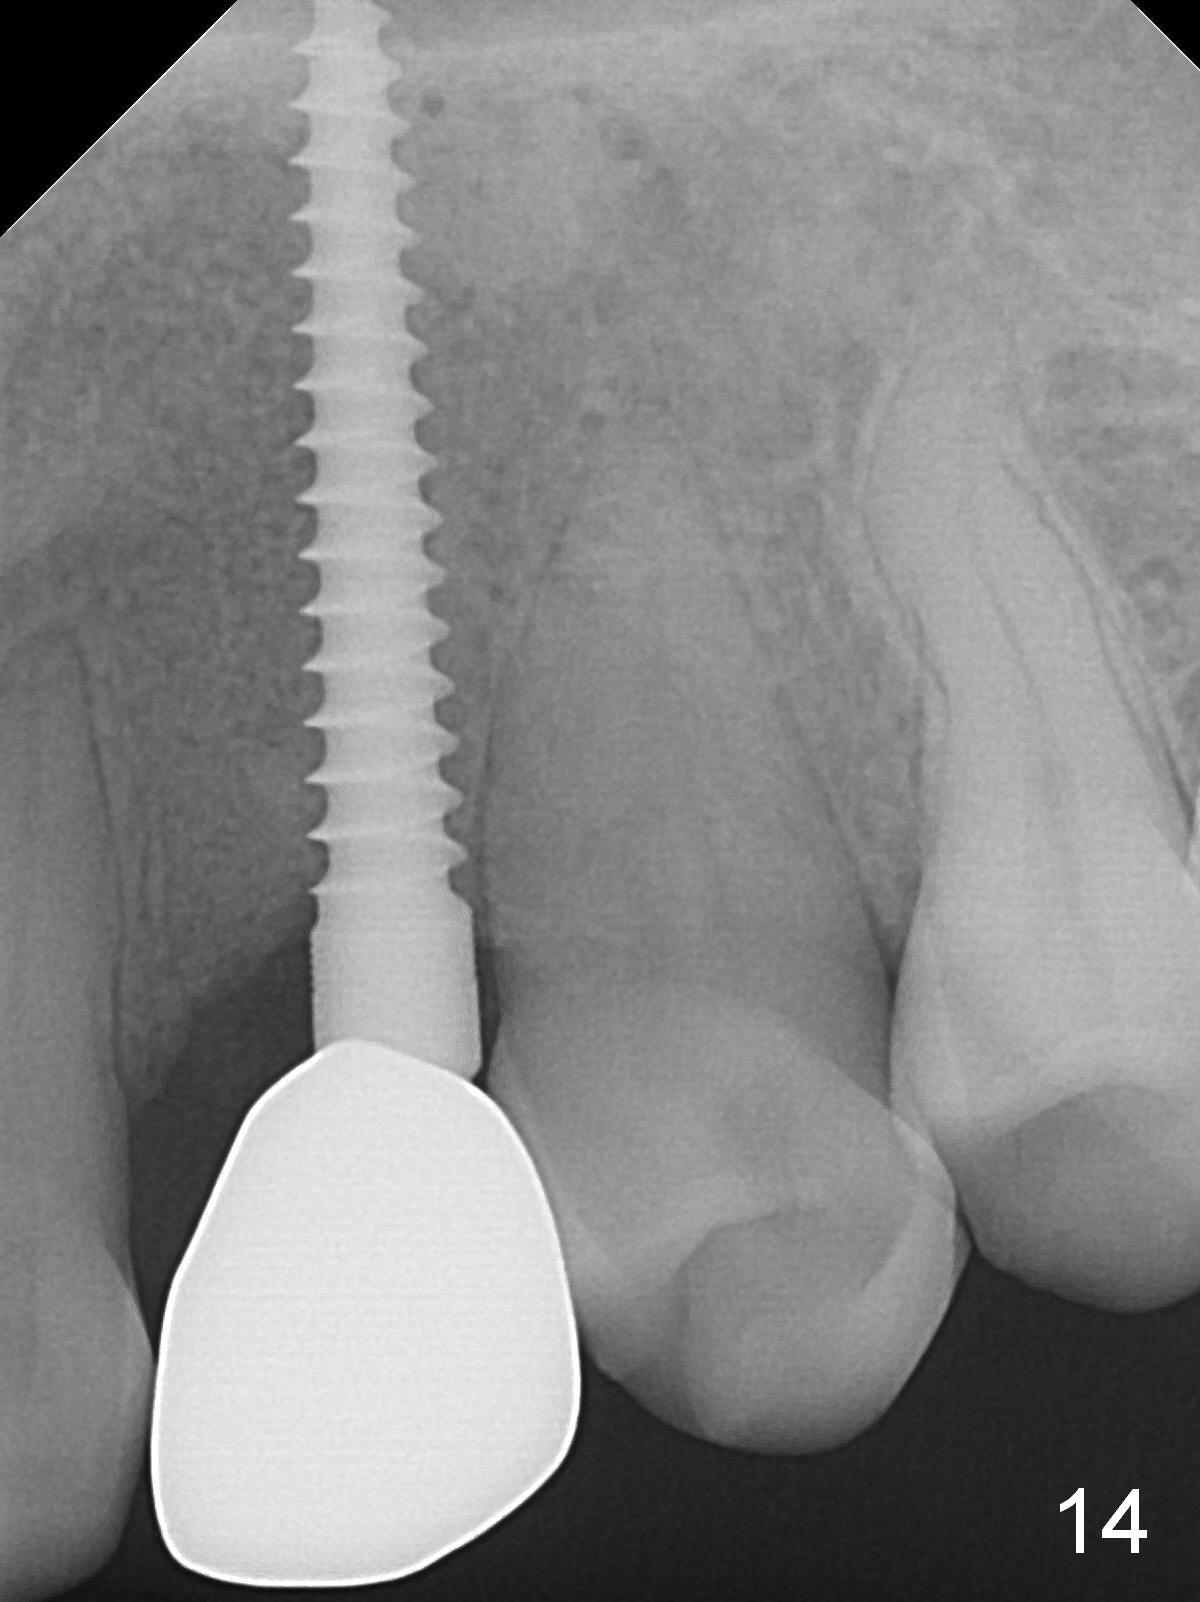

Intraop PA shows that the nasal floor is perforated (Fig.3). The patient experiences bilateral nasal obstruction. Sneezing produces trace of hemorrhage from the left nostril and large amount of secretion from both nostrils. The nasal speculum is misplaced in the clinic. Clinical nasal floor perforation cannot be confirmed. After abutment preparation, an immediate provisional is fabricated. Afrin is prescribed. Post-op instruction includes continuing Amoxicillin and Chlorhexidine rinse. A few hours postop, the patient reports no abnormality.

There is no gingival recesssion (data not shown) or bone loss around the implant 1 year post cementation (Fig.14).